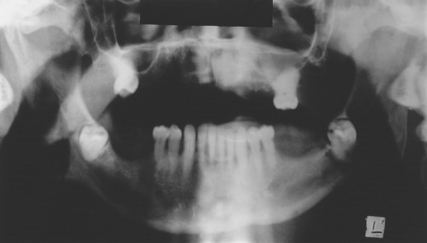

The maxillary sinus is often referred to as the maxillary antrum (or more simply the ‘antrum’). It is important to the dental surgeon because of its close relationship to the posterior maxillary teeth (generally from first premolar to third molar). The proximity varies between individuals (Fig. 15.1) but tends to increase with age as the antrum enlarges. The antrum can encroach into alveolar bone after tooth extraction, and periapical bone loss resulting from dental disease may further decrease the amount of bone separating it from the teeth. This close anatomical relationship can lead to diagnostic difficulties because both the antrum and the maxillary teeth are innervated by branches of the maxillary division of the trigeminal nerve. In addition, infection may spread from the periapical region of the posterior maxillary teeth to the antrum (and in the opposite direction) and the antrum is at risk of iatrogenic damage during certain dental procedures.

Fig. 15.1 (a) A small maxillary antrum that does not reach the apex of the second premolar. (b) A large maxillary antrum that reaches to the apex of the lateral incisor.